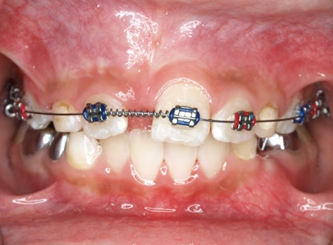

Răng thừa (a) làm R11 (b) bị kẹt không mọc ra được Tạo khoảng trước phẫu thuật

http://www.dentalnews.com/wp-content/uploads/2015/10/Maxillary-Central14.jpg =http://www.dentalnews.com/wp-content/uploads/2015/10/Maxillary-Central16.jpg =

Phẫu thuật lấy răng thừa sau 4 tháng tạo khoảng Chỉnh nha kéo R11 ngầm lên

Qúa trình chỉnh nha kéo răng cửa mọc ngầm hoàn tất

Hình 5: Minh họa phẫu thuật lấy răng thừa kết hợp với chỉnh nha ở một bé trai 9 tuổi